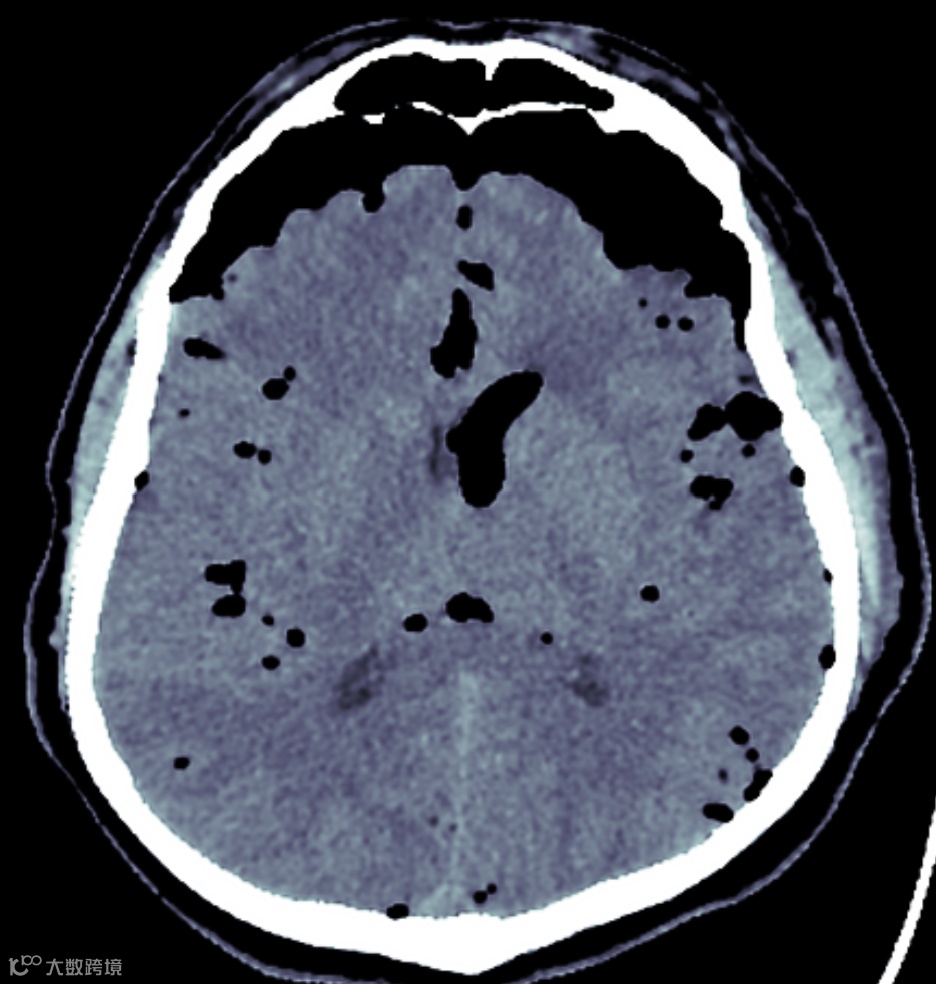

张力性气脑症的另一个影像学表现是蛛网膜下腔内多个小气泡影,称为气泡征。